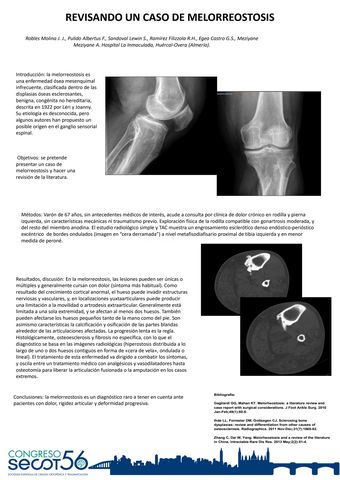

REVISANDO UN CASO DE MELORREOSTOSIS

Título: REVISANDO UN CASO DE MELORREOSTOSIS

Autores:

JUAN JOSÉ ROBLES MOLINA, FRANCISCA PULIDO ALBERTUS, SERGIO SANDOVAL LEWIN, RAFAEL RAMIREZ FILIZZOLA, GUILLERMO EGEA CASTRO, ANISS MEZIYANE